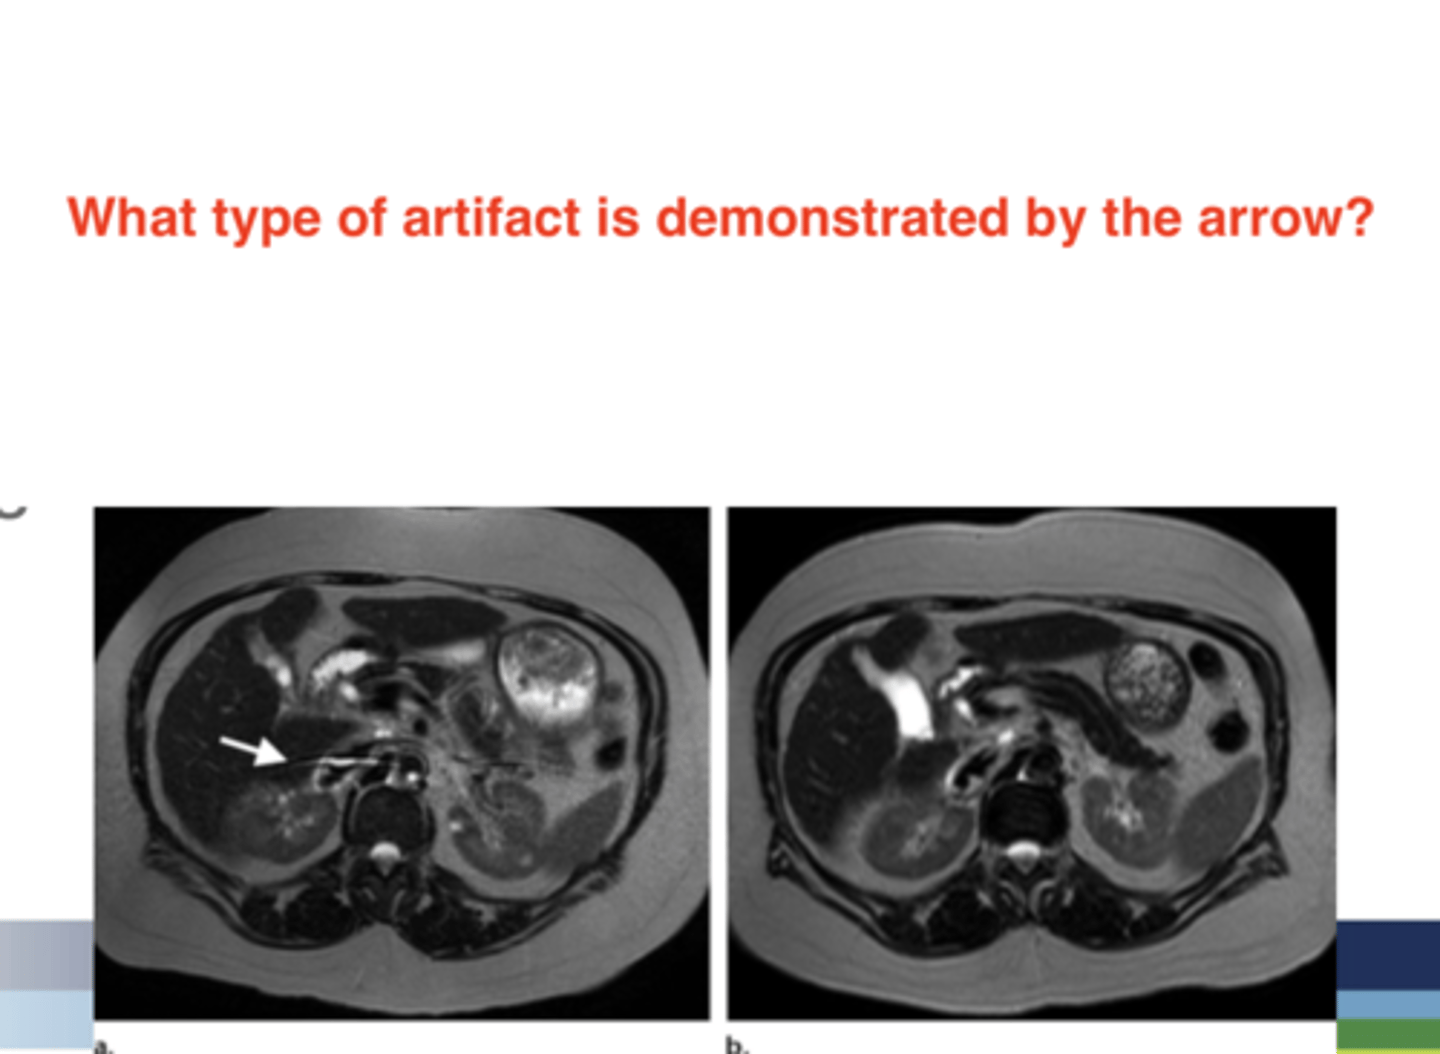

Magnetic Susceptibility Artifact

Chemical Shift

Out-of-Phase Signal Cancellation (Chemical Misregistration)